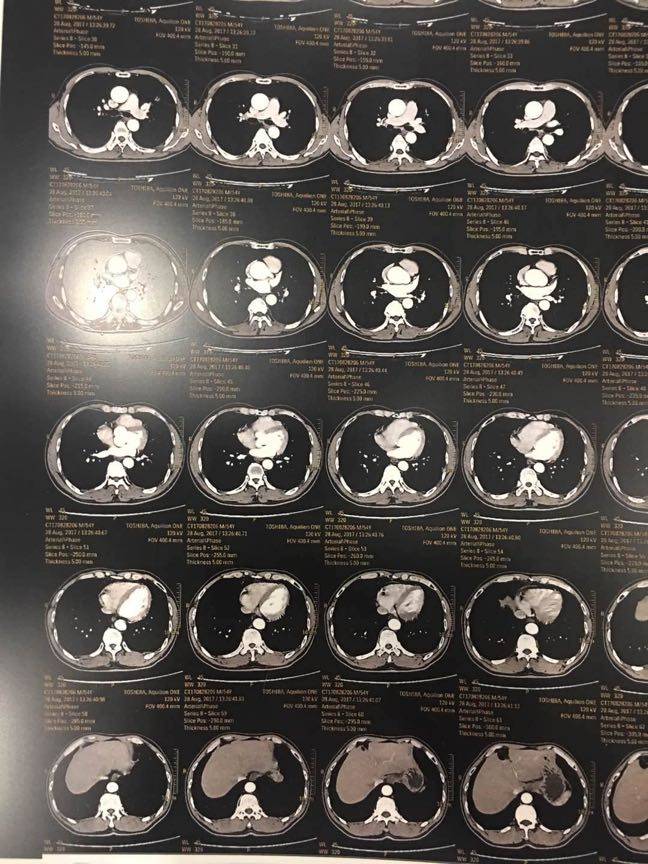

陈医生,这个是姐姐把两张胶片分8张拍的,会不会清楚点!

陈波医生

片子的日期写明一下